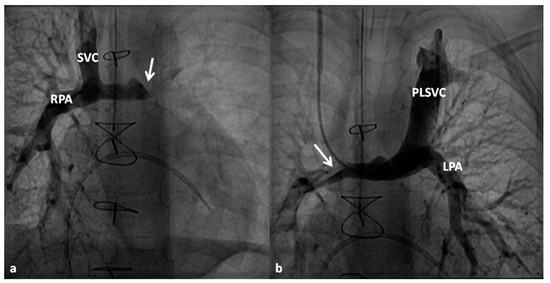

At about the age of six months, a bidirectional Glenn procedure [80] is performed. In this procedure, the superior vena cava (SVC) is disconnected from the right atrium and anastomosed to the PA so that the blood from SVC is directed into both branch PAs, thus the name bidirectional Glenn (Figure 8).

In patients with an additional persistent left SVC, a bilateral, bidirectional Glenn procedure (Figure 9) is performed especially if the bridging left innominate vein is small or absent.